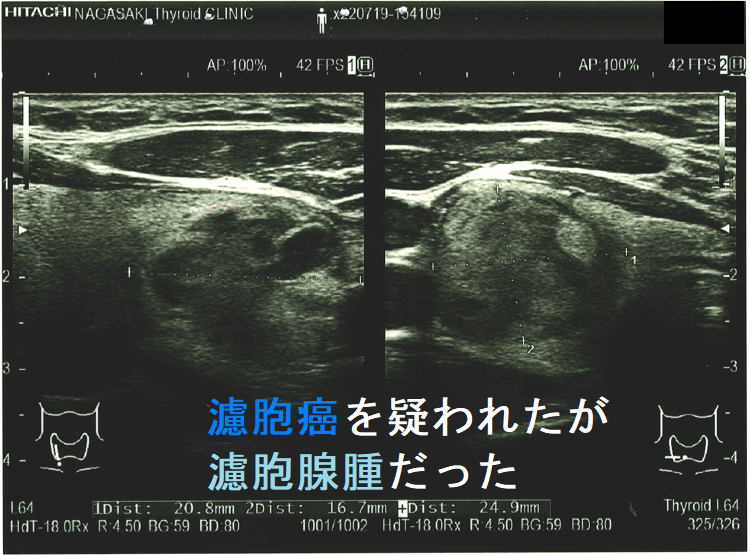

濾胞癌を疑われたが濾胞腺腫だった 超音波(エコー)画像;特に、中心部の極めて低エコーな箇所が疑わしい。。

実際、同じような見え方で甲状腺濾胞癌だったケースもあります(内部に低エコー領域が存在する甲状腺濾胞癌)。

ケース③

良性濾胞腺腫と甲状腺濾胞癌をエコーで鑑別するのは困難です。エコー上、周囲甲状腺組織への被膜外浸潤、あるいは甲状腺外浸潤を認めれば甲状腺濾胞癌です。